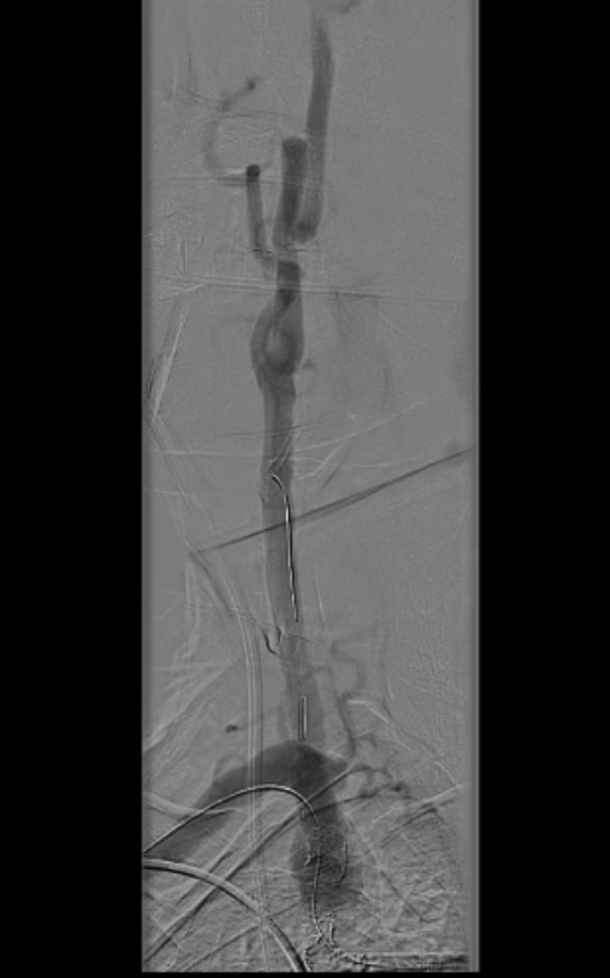

主动脉弓上造影显示无名动脉起始支架内重度狭窄,右椎动脉显影延迟,解除无名动脉支架内狭窄,恢复血流通畅,同时保障脑保护,降低并发症风险。

无名动脉起始支架内重度狭窄右椎动脉显影延迟

导丝与导管操作:超滑导丝配合多用途导管选入无名动脉,调整角度进入右锁骨下动脉;因主动脉弓扭曲严重,更换支撑导管通过病变段并造影证实

超选入无名动脉

无名动脉起始支架内

重度狭窄